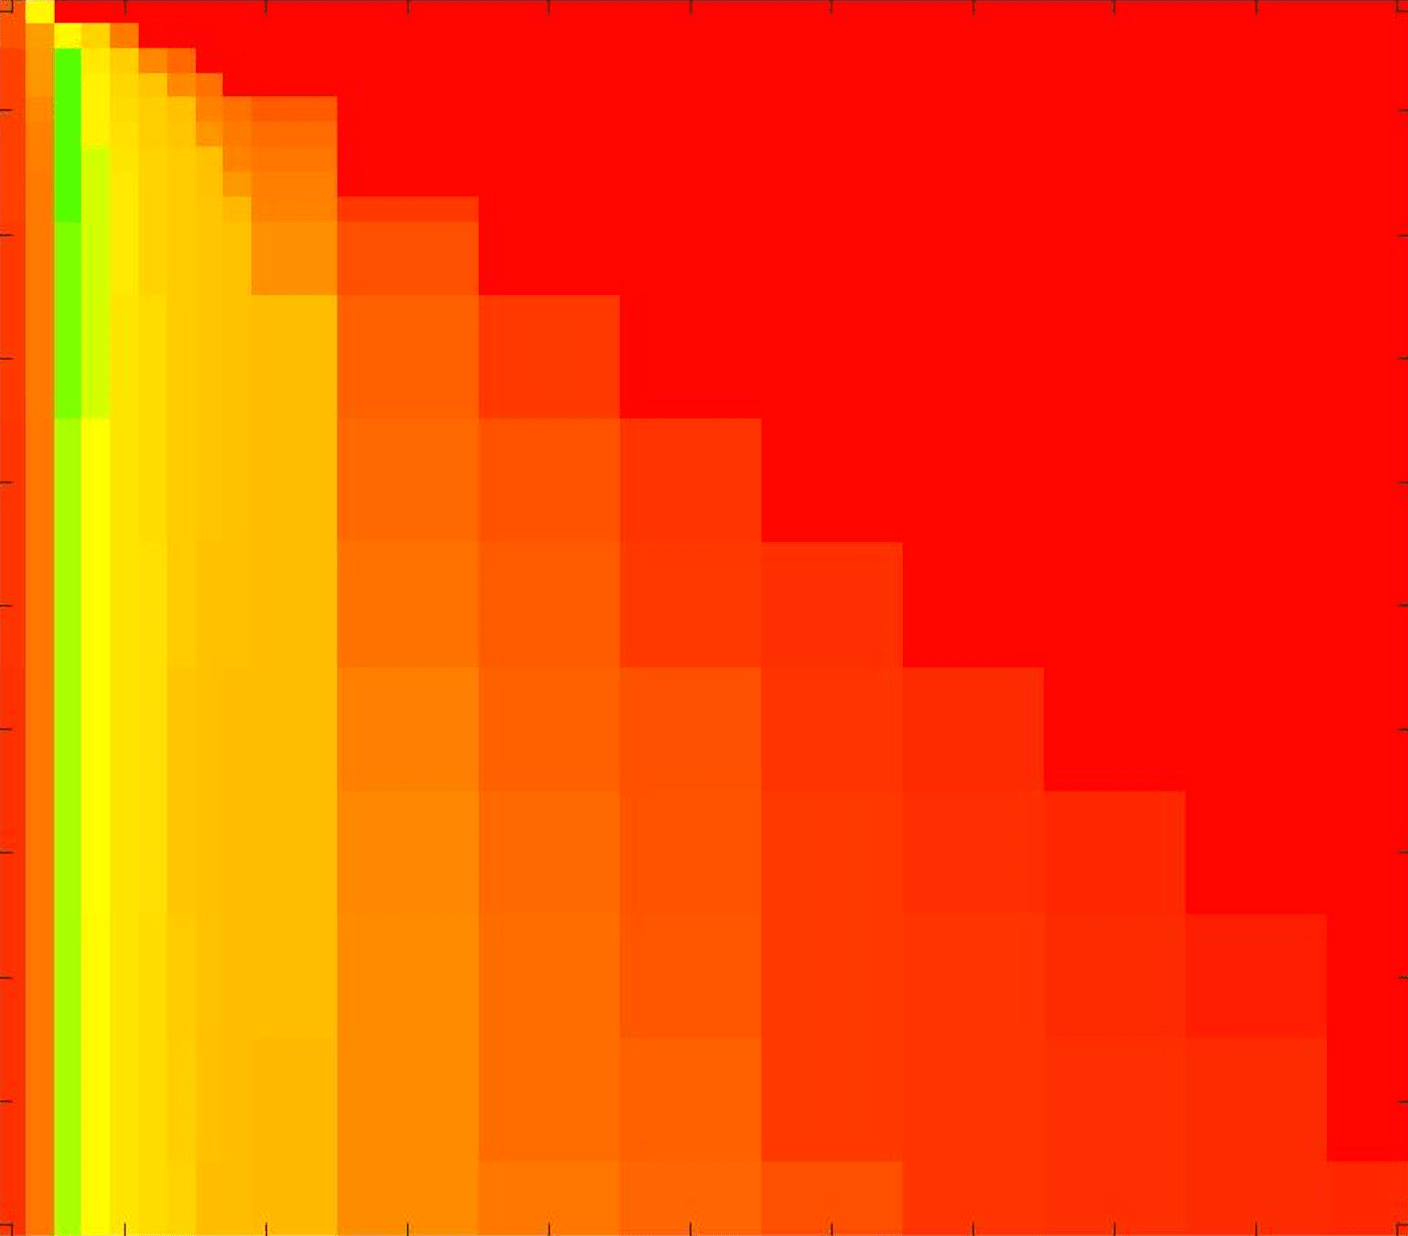

where refers to the number of points in the enclosed region. This takes values in the range , with higher TC values indicating a more accurate segmentation. In the following we will represent accuracy visually from red () to green (), with the intermediate scaling of colours used shown in Fig. 8. This will be particularly relevant in §7.2.

The TC values for the parameter sets are presented as heatmaps in Figs. 11–13. A heatmap is a convenient way to display accuracy results for hundreds of tests concisely. In Fig. 9 we give an example heatmap with the same axes used for those in Figs. 11–13. For each of the combinations of parameter values we give the TC value of the segmentation result and represent it by the appropriate colour. The corresponding colour scale is shown in Fig. 8. Qualitatively, the more green areas of the heatmap the more accurate the model is for a wider set of parameters. Example results for Test Image 5 when varying (with ) for the proposed model are given in Fig. 10. Here it can be seen what each accuracy result corresponds to visually.

Note. The axes have been removed from the heatmaps in Figs. 11–13 for presentational clarity. However, to be explicit, the axes used in all heatmaps are the same as those in Fig. 9.

Synthetic Images. These results are presented in Fig. 11. For Test Images 1–2 we see poor parameter robustness from all competing models, except for GAV which performs reasonably well. However, the proposed model has minimal parameter sensitivity for these images, with good results achieved for almost every combination of values tested. For Test Image 3 all models have a reasonable parameter range (except for RSF), however the proposed model gives better quality results for a wider parameter range. The other models achieve reasonable results here as the foreground intensity of the ground truth is greater than the background , whereas for Test Images 1–2 they are equal . These results highlight the key advantage of the proposed model.

Real Images. In Fig 12 we present results for Test Images 4–6. Here, the proposed model performs in a similar way to its competitors because these images are more typical selective segmentation problems in the sense that there is a clear distinction between the foreground and background intensities. In particular, the values in each case are: Test Image 4 , Test Image 5 , and Test Image 6 . It can be seen that the proposed model is competitive compared to previous approaches. The performance is quite poor for Test Image 5, but is arguably still the best for this challenging case. In Fig. 13 we present results for Test Images 7–9. Here the proposed model outperforms previous approaches significantly for each image. This is mainly due to the type of image considered. Specifically, the true intensities are: Test Image 7 , Test Image 8 , and Test Image 9 . The proposed model is capable of achieving results where , with other models failing completely in these cases.